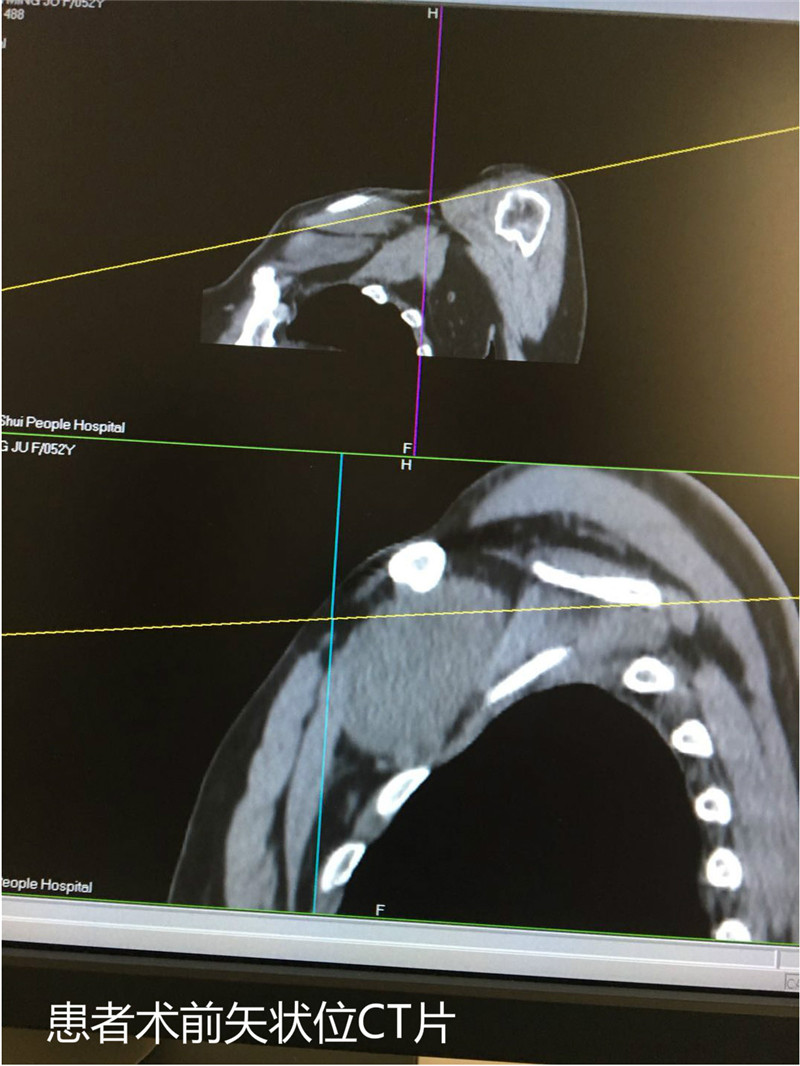

正常人的左侧锁骨下是臂丛神经、锁骨下动脉、静脉等重要组织,而杨大妈的左侧锁骨下却有一个直径约150px的大肿瘤。瘤子压迫重要的神经血管,导致杨大妈左手持续的麻木并进行性加重,该部位的瘤体在我院相对较为罕见。近日,杨大妈在我院骨科成功接受了左锁骨下肿瘤切除术,现术后情况良好。 今年5月份,家住石湫镇的52岁杨大妈逐渐出现左手麻木疼痛的症状,开始以为自己年纪大了的原因,后来病情逐渐加重。到6月份时大妈出现左手的肌力下降,干活或者持物都受到了严重的影响,遂就诊于我院。完善检查发现,血管神经明显受压,急需手术解除压迫。左锁骨下区域的肿瘤,邻近区域都是重要的血管及神经,一旦术中无意损伤,那对患者而言将是致命的打击,甚至因出血无法止住而导致死亡。 “左锁骨下肿瘤这么大,且生长的位置靠近臂丛神经及大血管非常罕见,阅读CT可见左侧头静脉已被压扁,做上肢的血液供应已受波及,且肿瘤正不断的变大,压迫症状在患者身上越来越明显。”骨科陈优民主任看到CT时很惊讶。他介绍,经过穿刺活检,确诊为神经纤维瘤。患者入院后,由于考虑到肿瘤源自神经,且压迫症状已严重影响到患者的生活,如果放任瘤体继续发展,甚至有危及患者生命的可能,手术是唯一救治方法。但要切除这个部位的瘤体,风险性极高,一是瘤体的解剖位置特殊,隐藏于左侧锁骨下,手术空间非常小,进而手术视野范围也小,大大增加了手术难度;二是瘤体来源于神经组织,在手术剥离过程中如果不能完整剥离则需要姑息性切除,但这样术后复发的几率依旧很大,瘤体引发的症状仍然会卷土重来;三是瘤体位置邻近大的锁骨下动静脉,若是术中损伤,可能因出血而给患者带来生命危险,另瘤体表面也有丰富的滋养血管,所以术中极易引起大出血。 术前,由医务科组织全院多学科会诊讨论患者的诊疗,并制定了最佳手术方案。由胸外科的全勇辉主任与骨科陈优民主任与一起协同手术。术中,医生们打开左侧锁骨下皮肤、脂肪、筋膜、肌肉等组织,在保护周围血管及神经的情况下,小心地将瘤体切除。经过测量,瘤体约150px*125px*100px大小,如一个大大的“桃子”。术后,杨大妈恢复良好,左手疼痛症状明显改善,麻木情况也较术前好转,复查胸部CT肿瘤已完全切除,被压迫的血管也已复张。